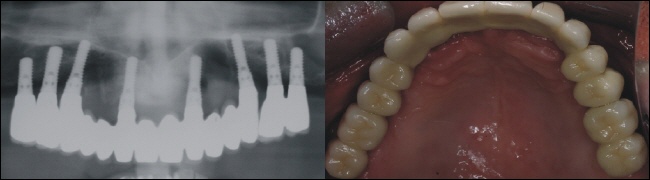

Acht Implantate bieten im Oberkiefer eine solide Basis für eine festsitzende Brückenkonstruktion. Auf dem Bild oben rechts sieht man die Implantatkappen in der Mundhöhle. Die Implantate müssen nun wiederum 4-5 Monate im Knochen einheilen.

Versorgung - festsitzende Brücke

Das Röntgenkontrollbild oben links zeigt den exakten Sitz der Brückenkonstruktion. Oben rechts sieht man die einzementierte Brücke im Mund. Die Versorgung ist nur auf den Kieferkamm begrenzt, das heiß der ganze Gaumen ist frei. Dies bietet höchsten Komfort und ein ästhetisches Optimum, ganz so wie bei den eigenen Zähnen.